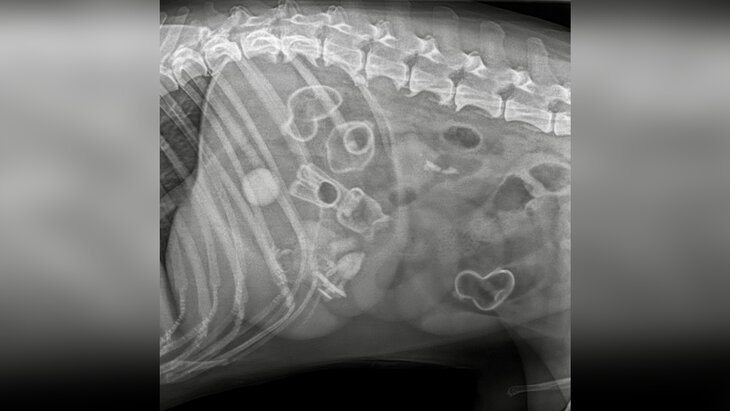

Собаку, которая проглотила несколько детских игрушек, прооперировали в ветклинике. Об этом сообщает госветуправление Нижнего Новгорода в соцсети "ВКонтакте".

В ведомстве отметили, что семилетний самоед на протяжении трех дней чувствовал себя плохо, поэтому его хозяева обратились в госветклинику Канавинского района. После того как псу сделали рентген, врачи обнаружили в желудке и кишечнике животного сразу несколько инородных тел, включая уточку, лошадку и скрепыши.

Врачи удалили все игрушки из желудка и кишечника животного.